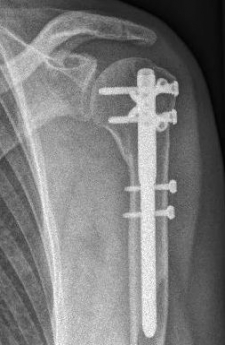

Picture: Here is a subcapital upper arm break in a young woman. An angle stable plate osteosynthesis was performed to stabilize the head in correct position to the humeral shaft and shoulder joint. Especially in young patients, We strive to treat non-invasively and as gently as possible. This possibility is often due to the bone quality in young as opposed to older people.